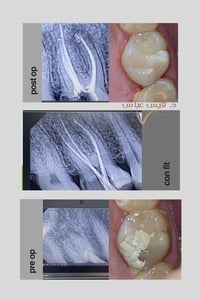

#حشوة_جذر #حشوة_تجميلية علاج عصب لسن خلفي مع إعادة ترميمه بحشوة ضوئي...